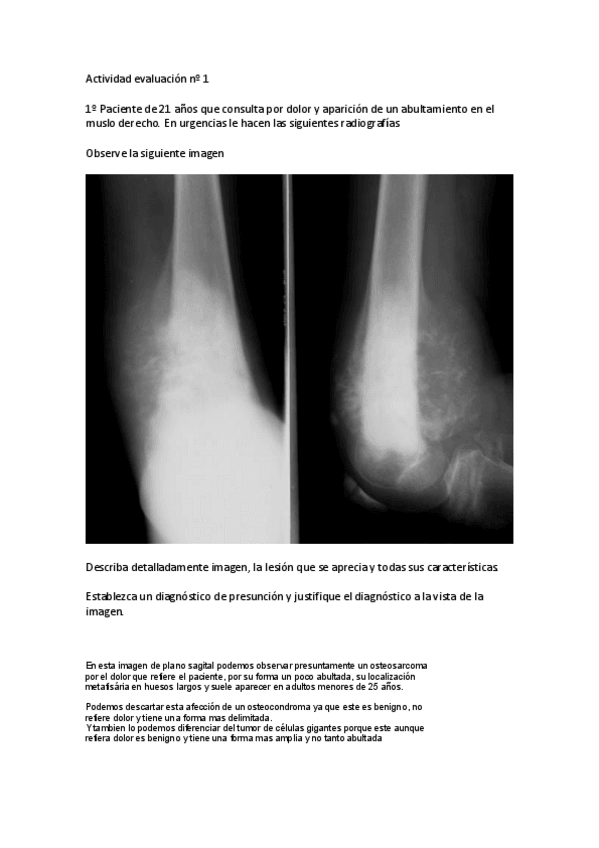

He publicado nuevos apuntes de 2º Afecciones médico-quirúrgicas I: Actividad-evaluacion-2.pdf

He publicado nuevos apuntes de 2º Afecciones médico-quirúrgicas I: Actividad-evaluacion-1.pdf